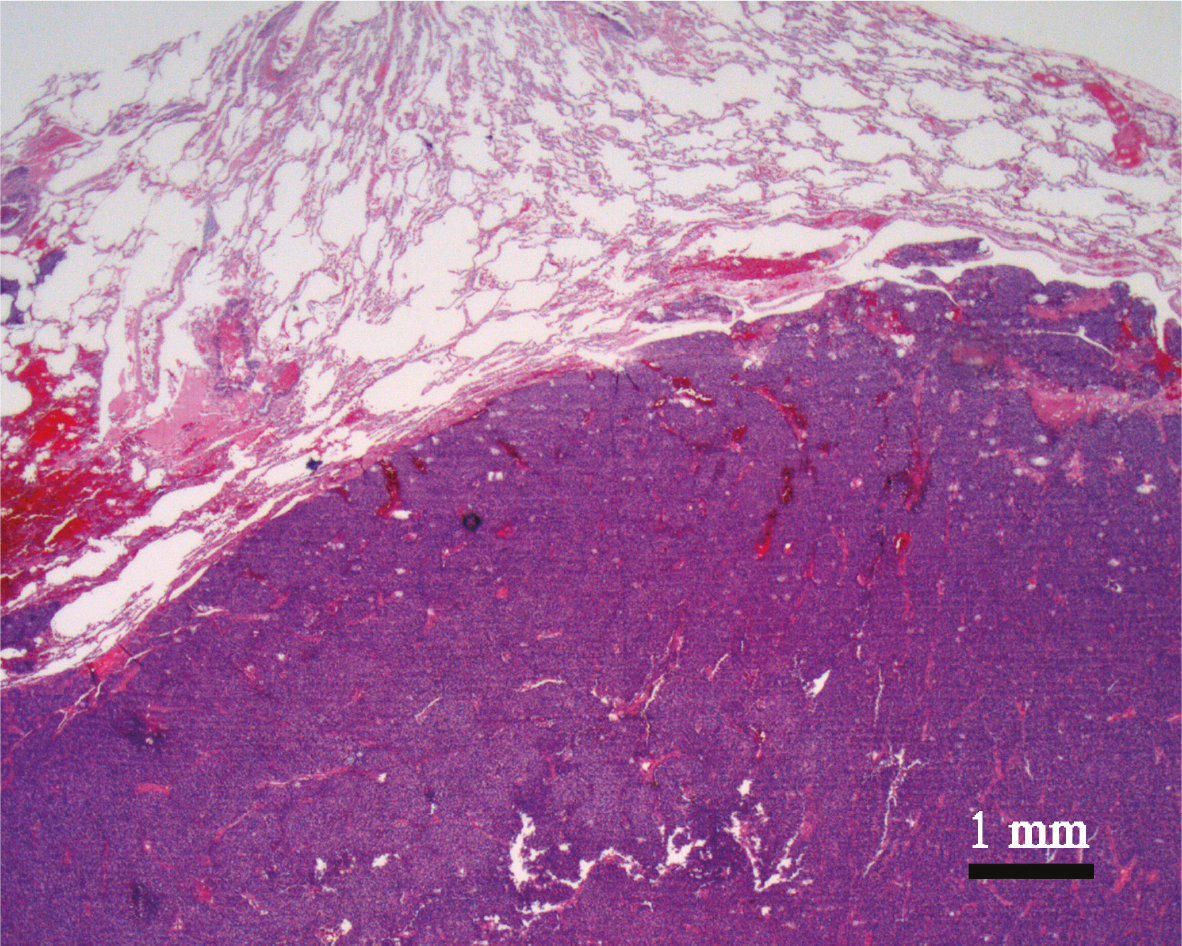

Histologically, ES/PNET is a “round blue cell tumor” that is characterized by predominantly undifferentiated sheets of cells with relatively little stroma. It may be found at the skeletal site of origin or at metastasis (Figure 1). The cell size may vary with some ES composed of small round cells with round nuclei containing fine chromatin, scanty clear or eosinophilic cytoplasm, glycogen granules highlighted by Periodic Acid Schiff (PAS) staining, and indistinct cytoplasmic membranes (Figure 2). On the other hand, some ES/PNETs are made up of larger cells with prominent nucleoli and irregular contours. The tumor cells contain abundant glycogen, which is highlighted by histochemistry (PAS). In some cases, an arrangement of the tumor cells around a pseudo lumen (Homer-Wright pseudo-rosettes) is seen. Necrosis is a standard feature, and non-necrotic viable areas show tumor cells with frequent perivascular distribution (7).

Fig 1

Figure 1. Blue cell tumor. The microphotograph depicts a resection specimen of the lung showing a “round” blue cell tumor involving the right lower half portion of the picture (dark blue area). The tumor is well demarcated and the intensity of the tumor cells is identifiable easily comparing to the alveolar parenchyma of the lung of the left upper half of the picture. The “roundness” of the tumor cells with round-ovoid contour is not appreciable at this magnification, but is better identifiable in figure 2 (Hematoxylin and Eosin staining x 12.5 original magnification).